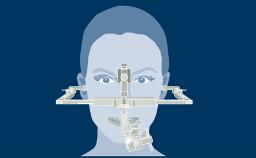

O uso de implantes dentários tornou-se um tratamento padrão em muitas situações clínicas. No entanto, para alcançar resultados funcionais e estéticos ideais, o clínico deve avaliar a complexidade e os riscos associados a uma terapia de implante antes de iniciar o tratamento. O sistema de classificação SAC diferencia entre tratamentos simples, avançados e complexos. A 2ª Edição totalmente revisada da Classificação SAC em Implantodontia foi atualizada para garantir consistência com a prática contemporânea de implantes. A nova versão do SAC Assessment Tool também está disponível aqui.

- descrever os determinantes da Classificação SAC

- descrever o processo usado para desenvolver uma classificação

- selecionar a complexidade do caso usando a ferramente de Avaliação SAC Online